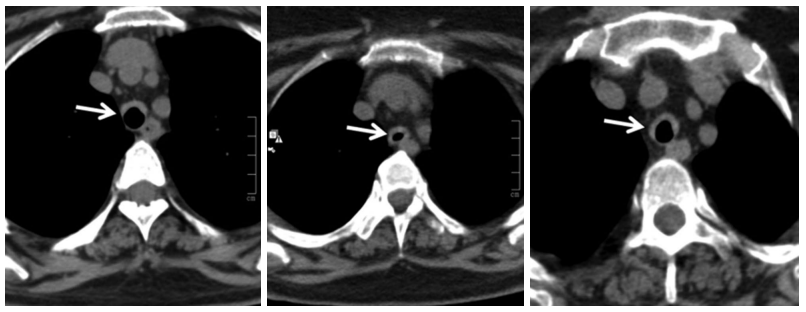

In January 2017, she presented with two- week history of worsening of shortness of breath, wheeze and stridor. Further evaluation showed interval increase in circumferential thickening of trachea and bilateral main stem and lobar bronchi on HRCT of the chest and neck. However, repeat ANCA was negative for both proteinase 3 and MPO by line immunoassay and by indirect immunofluorescence for cytoplasmic and peri-nuclear ANCA. After initial treatment with broad-spectrum antibiotics and increased steroid dose, she had a marginal improvement. Considering this as a disease relapse, she was given rituximab 2 g two weeks apart. At subsequent follow-ups, the patient was doing well with just oral prednisolone 5 mg daily. At fourth month follow-up, HRCT of the chest with neck cuts was repeated and it showed reduction in wall thickening as compared to the previous scans (Figure 2). This time, the patient was given early rituximab 500 mg maintenance therapy and discharged on same dose of oral prednisolone and cotrimoxazole.